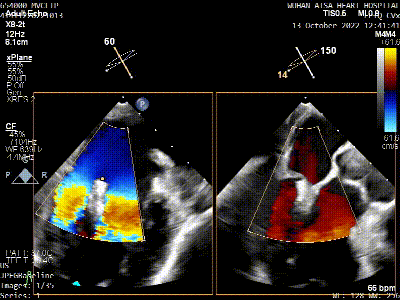

术前TEE评估

原发性二尖瓣反流(DMR),后叶P3区脱垂,反流程度4+,EROA 0.40cm2、RV 39ml;二尖瓣瓣口面积5.37cm²;二尖瓣前叶(A3)长度14.0mm,二尖瓣后叶长度(P3)长度12.2mm,脱垂宽度8.2mm,脱垂高度1.4mm;RA 2.9cm ,LA 3.6cm,左室射血分数LVEF56%,术前测量最大房间隔穿刺高度4.0cm

将MitraClip™XTR送入左房,由于左房太小,在达到骑跨过程中反复推进回撤CDS和稳定器,同时旋转SGC,达到骑跨的同时,保证Clip头端游离,且SGC在左房有深度。旋转M,同时顺时针往后旋转SGC借高度,使Clip垂直二尖瓣环平面,由于穿刺高度不够,Clip直接进入左室,这意味着操作要十分小心,左室组织复杂,稍有不慎将会造成组织损伤。使用A/P Konb中“A”旋钮借高度。确认垂直后,直接在左室打开Clip,3D外科视角,逆时针旋转使Clip夹臂处于11点-5点方向,回拉稳定器,使Clip处于3区脱垂区域,用“+/-”Knob中的“-”旋钮,使Clip更往后叶的同时增加操作高度,抓捕脱垂的瓣叶,关紧Clip后,反流从4+降低至0级,平均跨瓣压差2mmHg,左右肺静脉逆流均改善。前后叶活动度降低,后叶插入长度9mm,前叶插入12mm, 确认稳定性后释放Clip。释放后,即刻效果十分满意,手术圆满结束。